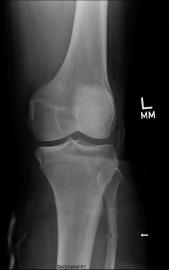

X-Rays Following Hyperextension of Left Ankle (January 31st 2006)

These x-rays were taken following a fluke event where Liam hyperextended his left ankle while playing an XBox 360 video game. As can be

seen in the images there are two (2) breaks that were produced from the hyperextension. One of the tibia bones has a hairline break and

the bone piece that spontaneously fused the tibia to the fibula has snapped. It took almost 2 weeks to determine that these breaks had

occurred. Due to Liam’s unique pain threshold and the lack of visible indicators, a break was not considered. Just another senseless

accident that resulted from the use of a violent video game. ;-) Yeah, right...